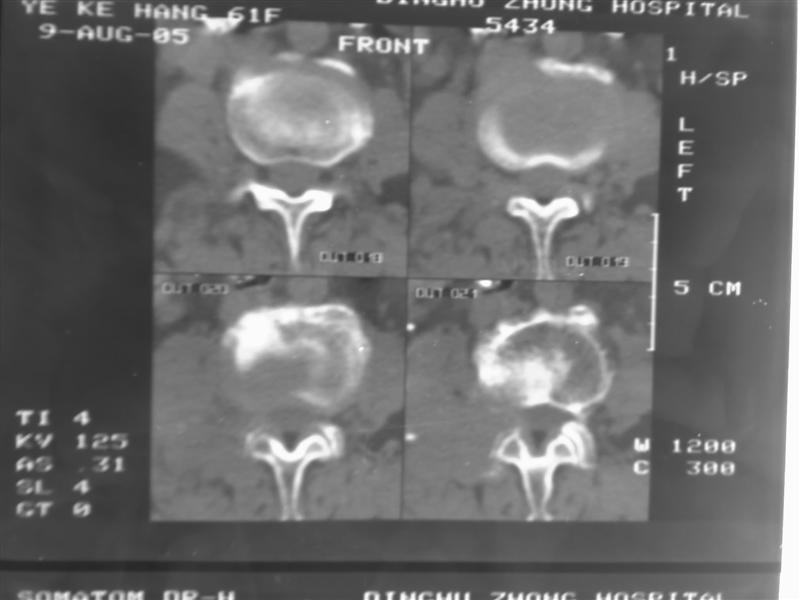

以下是引用guzhongliangddd在2007-9-27 13:42:00的发言:[br]首先考虑是转移性肿瘤.

以下是引用老爱克斯新网客在2007-9-27 17:59:00的发言:[br]多个椎体及椎弓跟骨质破坏,并见软组织肿块,符合转移瘤改变,

以下是引用wqs571018在2007-9-27 16:48:00的发言:[br]支持:多发病变,骨质破坏伴软组织块影,符合转移.